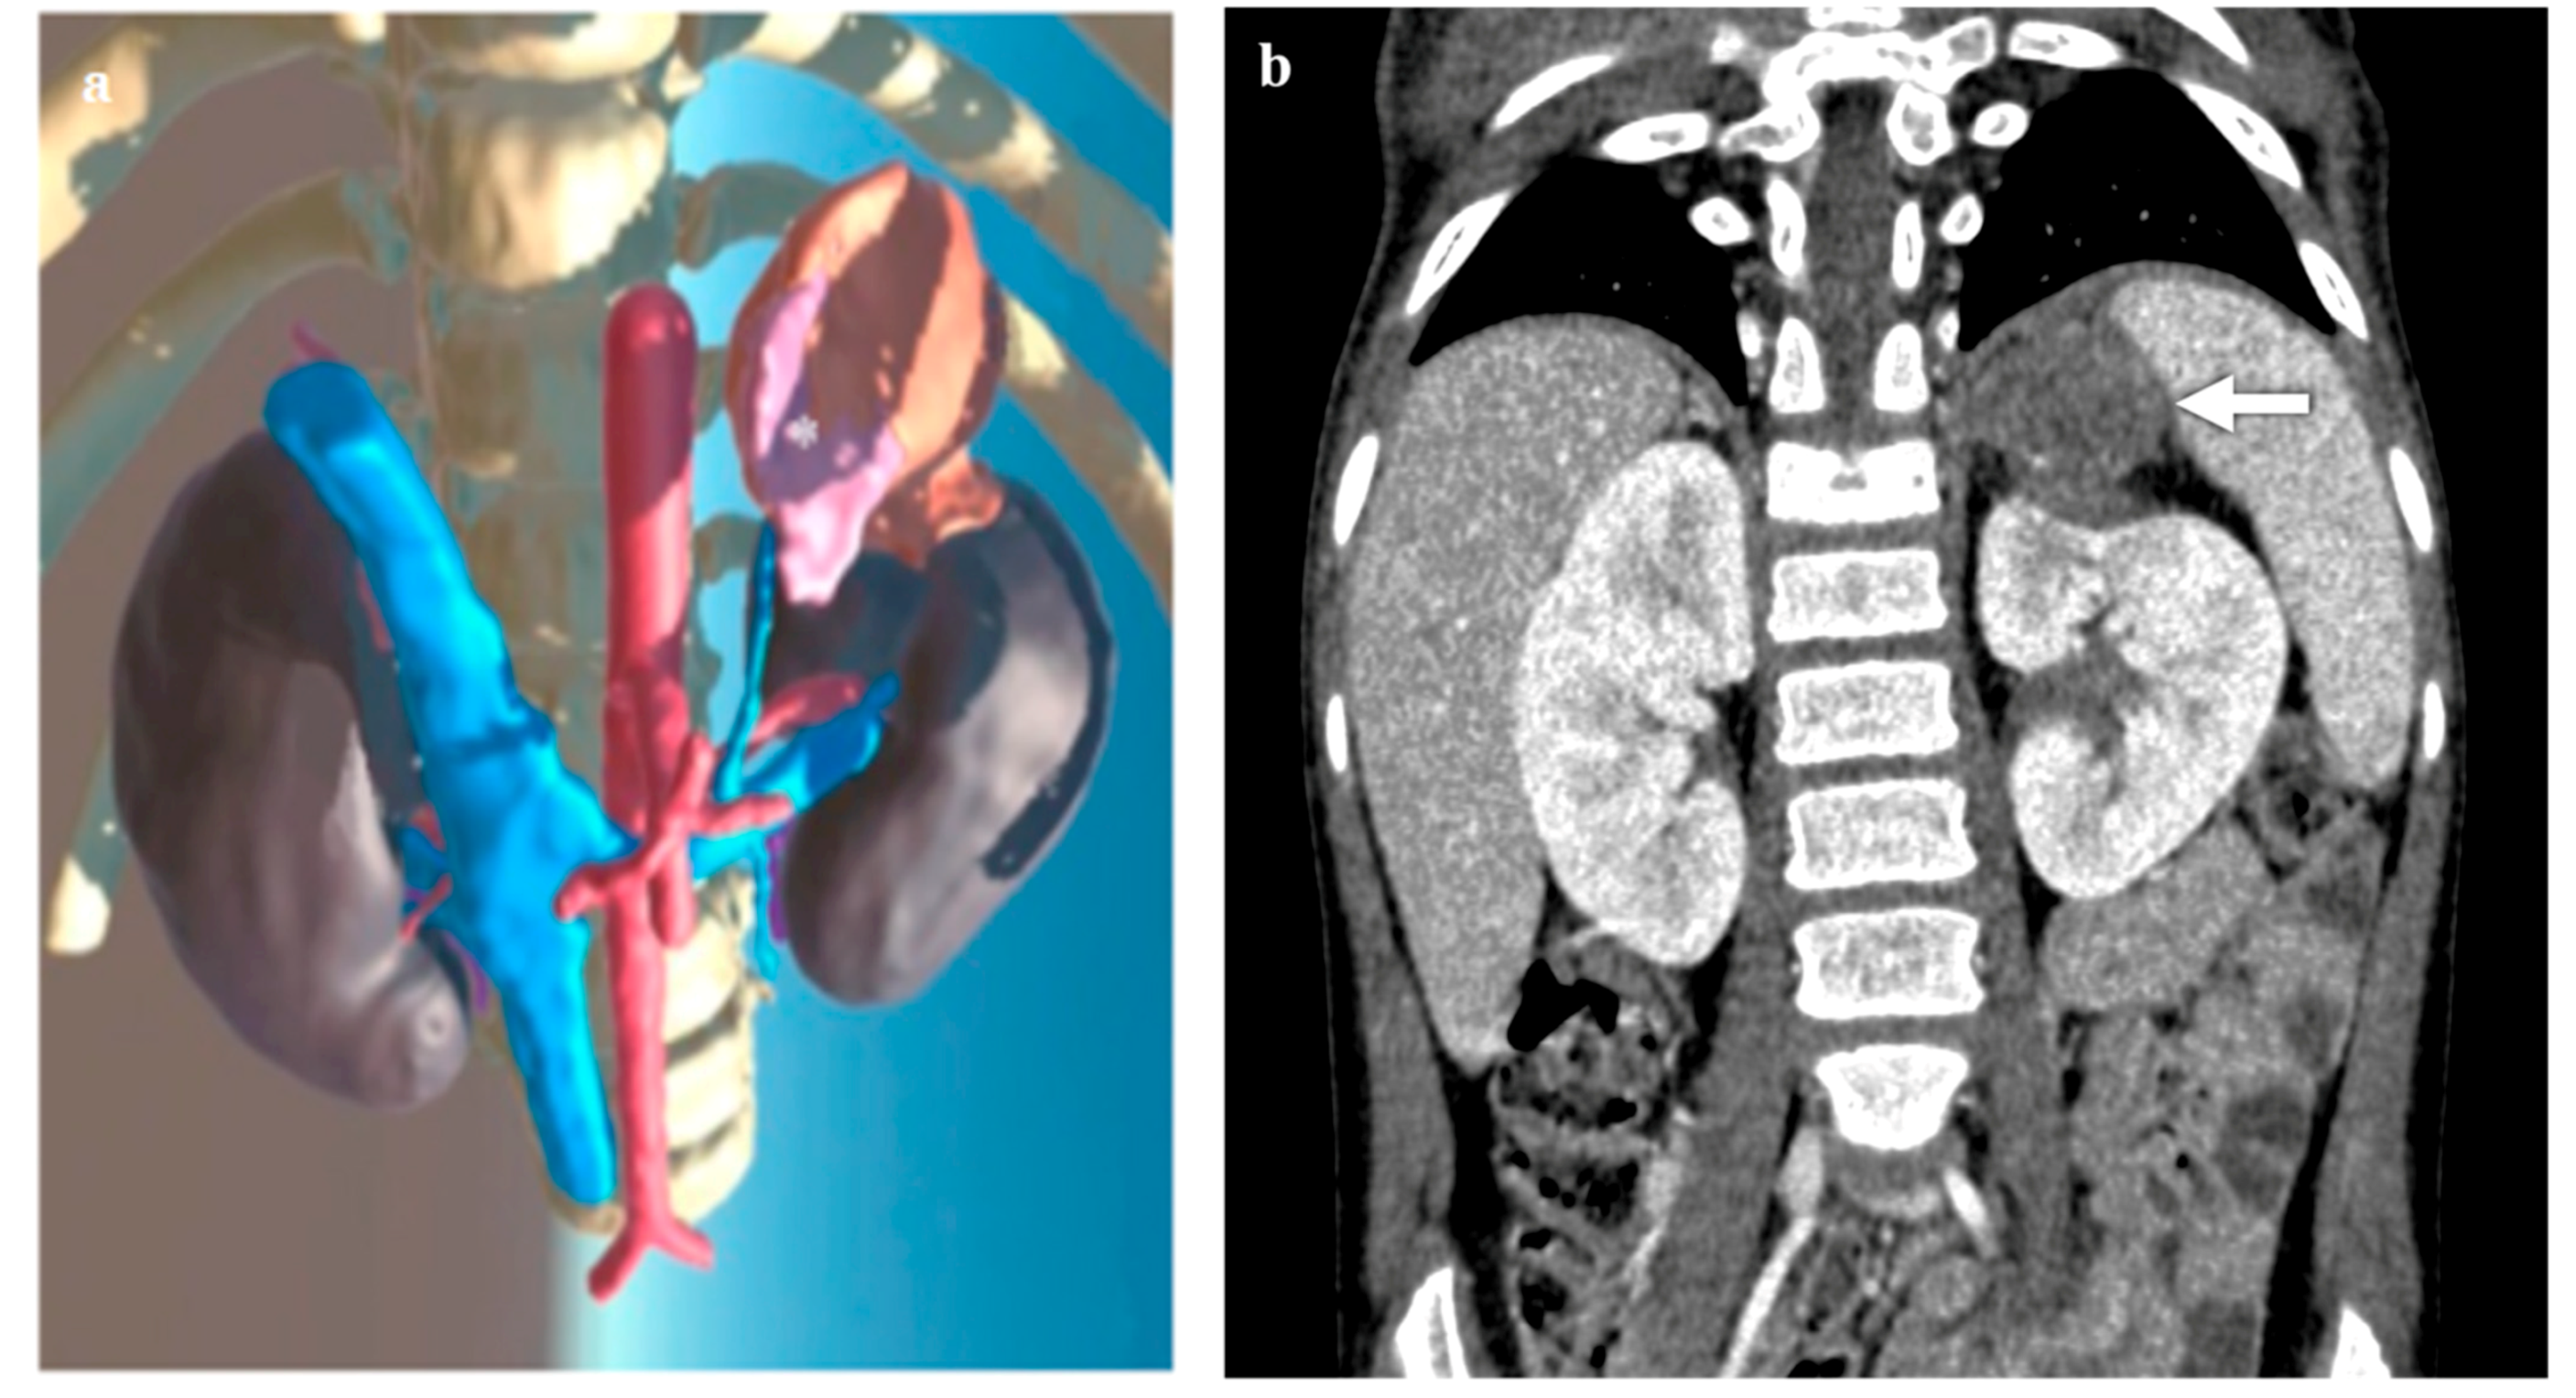

3.2. Adrenal Lesions

3.3. Kidney Lesions and Congenital Anomalies